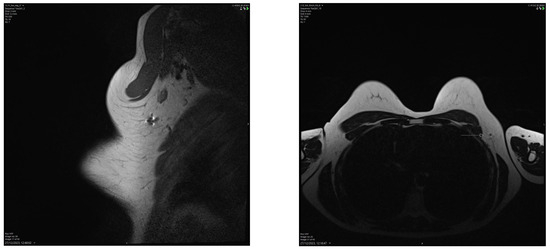

4.3. Imaging Modalities for Axillary Monitoring